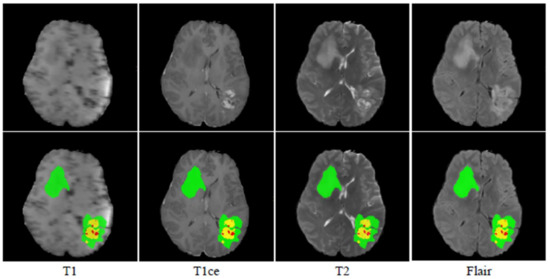

The BraTS 2020 dataset [22,23,24,25] is used in this research to evaluate the performance of the proposed network. There are 369 training, 125 validation, and 169 test multi-modal brain MR studies.T1-weighted (T1), post-contrast T1-weighted (T1ce), T2-weighted (T2), and fluid-attenuated inversion recovery (Flair) sequences are included in each study, as shown in Figure 4. The size of all the MR images is 240 × 240 × 155. In addition, experts annotated the enhancing tumor (ET), peritumoral edema (ED), as well as the necrotic and non-enhancing tumor core (NET) for each study. For online evaluation and final segmentation competition, the annotations for training studies are made public, whereas the annotations for validation and test trials are kept withheld.

Figure 4. MRI images and their ground truth for various modalities. Green, red, and yellow highlight the ED, NET, and ET areas, respectively.